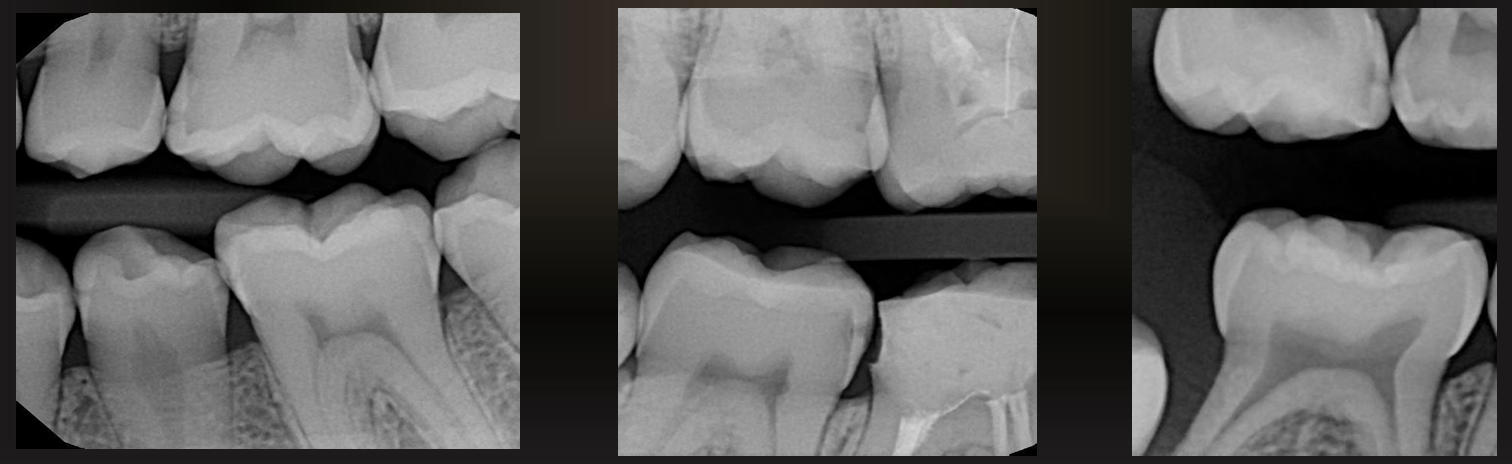

what are these?

large occlusal caries

small occlusal caries

radiographs are not very effective at detecting, may be seen as thin radiolucent line or cup shaped zone underlying occlusal enamel

minimum or no changes in enamel

what are these arrows pointing at? (except for 2nd molar in image D)